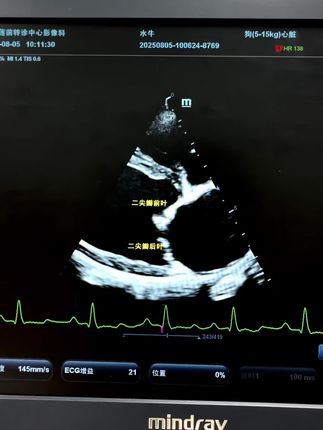

犬二尖瓣脱垂测量 #兽医 #心脏超声